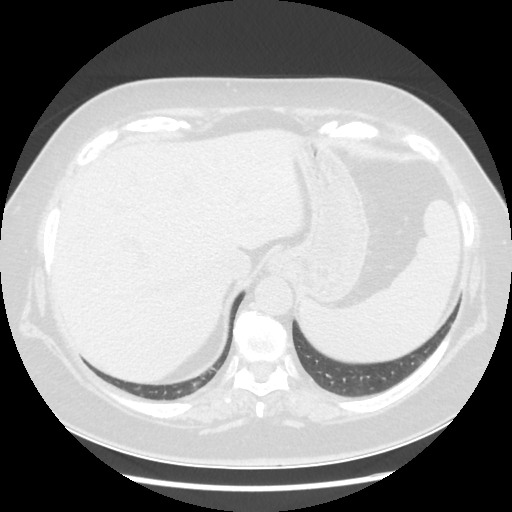

Original VENOUS CT scan

No window - Raw intensity values